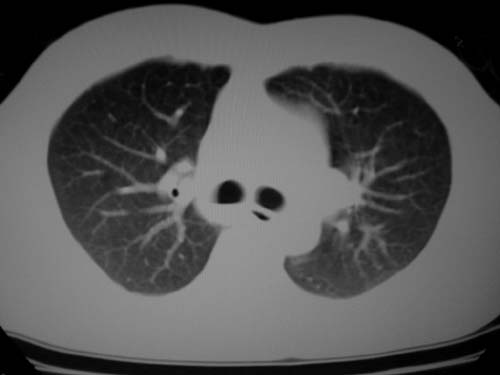

标题: CT19540: 31岁。自述结核性胸水治疗两个月后,在外院拍x线发 [打印本页]

标题: CT19540: 31岁。自述结核性胸水治疗两个月后,在外院拍x线发

右侧胸壁结节状软组织影伴相应肺叶内受侵,伴右侧胸腔积液。考虑:结核性可能大。

1、炎性病变,结核可能;2、右侧少量胸膜积液。

右侧胸壁结节状软组织影伴相应肺叶内受侵,伴右侧胸腔积液,结合临床,首先考虑结核。

考虑结核性胸膜炎,胸膜肥厚,不除外胸膜间皮瘤可能,建议复查。

支持结核,胸膜间皮瘤不排除.

1)考虑右侧结核性胸膜结节。2)右侧胸膜增厚+包裹性胸腔积液。